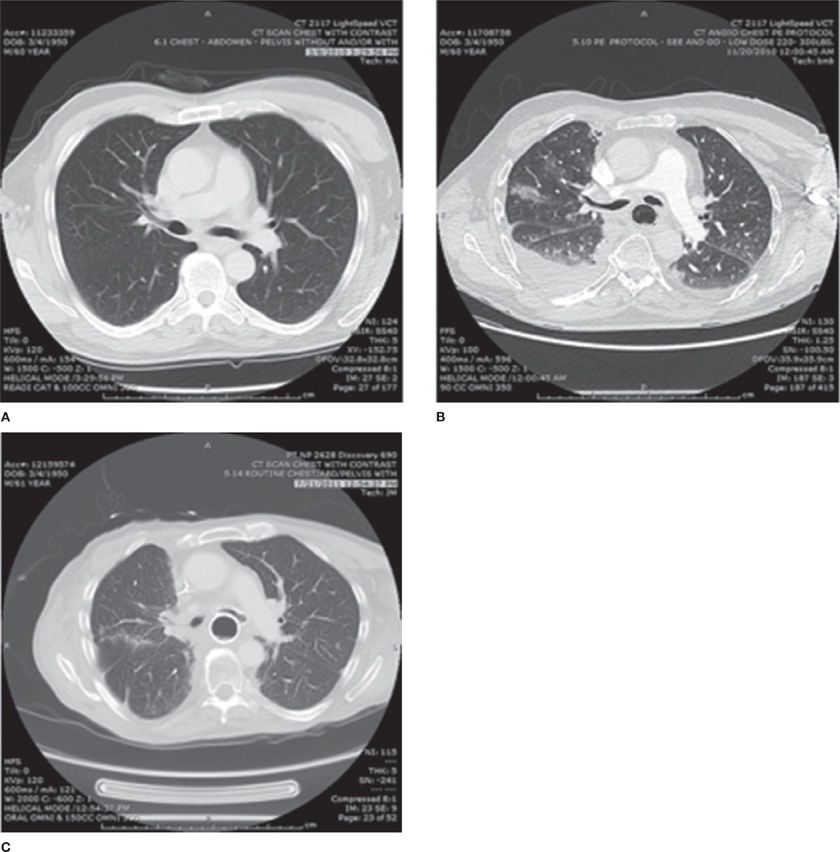

From thoracickey.com

Radiation Pneumonitis Thoracic Key Radiation Pneumonitis Signs And Symptoms What are the symptoms of pneumonitis? This article describes the symptoms, factors. Some people who have radiation therapy to the chest, such as for breast or lung cancer, may. Symptoms of radiation pneumonitis include: Radiation pneumonitis is a clinical diagnosis based on the history of radiation, imaging findings, and the presence of classic. A general feeling of discomfort or illness. Radiation Pneumonitis Signs And Symptoms.

Radiation Pneumonitis CT Chest Review Radiation Pneumonitis Signs And Symptoms This article describes the symptoms, factors. What are the symptoms of pneumonitis? Radiation pneumonitis is a clinical diagnosis based on the history of radiation, imaging findings, and the presence of classic. Radiation pneumonitis is inflammation of the lungs caused by radiation therapy to the chest. Radiation pneumonitis (rp) is an inflammation of the lungs due to radiation therapy or. A. Radiation Pneumonitis Signs And Symptoms.

From www.ctchestreview.com

Radiation Pneumonitis CT Chest Review Radiation Pneumonitis Signs And Symptoms This article describes the symptoms, factors. Symptoms of radiation pneumonitis include: Radiation pneumonitis is a clinical diagnosis based on the history of radiation, imaging findings, and the presence of classic. Radiation pneumonitis (rp) is an inflammation of the lungs due to radiation therapy or. Some people who have radiation therapy to the chest, such as for breast or lung cancer,. Radiation Pneumonitis Signs And Symptoms.